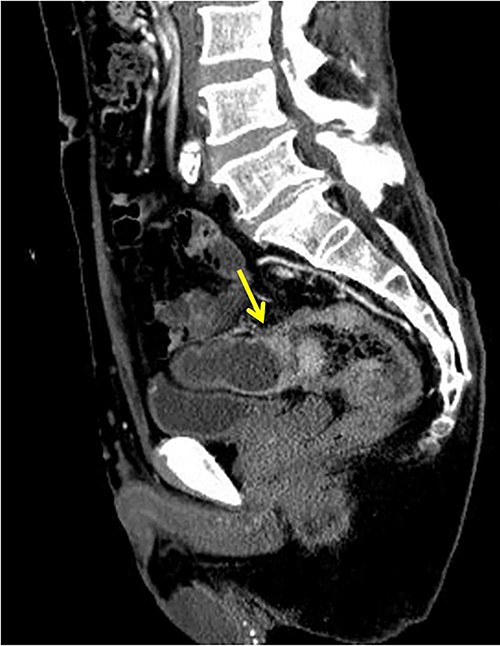

The operative time was 234 min, and the blood loss volume was 155 ml. Histopathological analysis revealed numerous lymph node metastases within the mesentery of the small intestine, and the patient was diagnosed with pT4b (small intestinal mucosa) N3 (28/41) M1 (small mesenteric lymph node 6/8) f Stage IV (TNM classification), nonsolid type (por2) adenocarcinoma, ly3, v2 (Fig. 4a and b). After receiving chemotherapy, she died 18 months after surgery.

(a, b) Descending colon cancer with small intestine invasion and fistula formation.